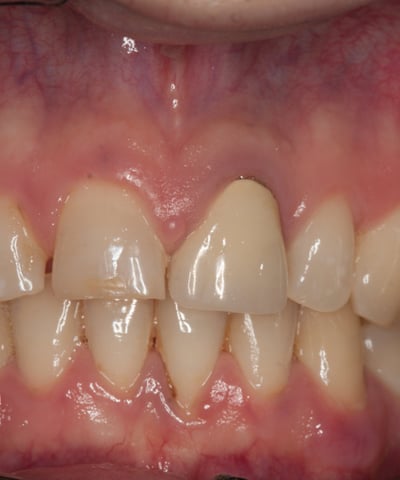

Prima:

Corona visibilmente discromica rispetto ai denti naturali.

Decementazione frequente della corona.

Perno moncone non funzionale e trattamento endodontico insufficiente.